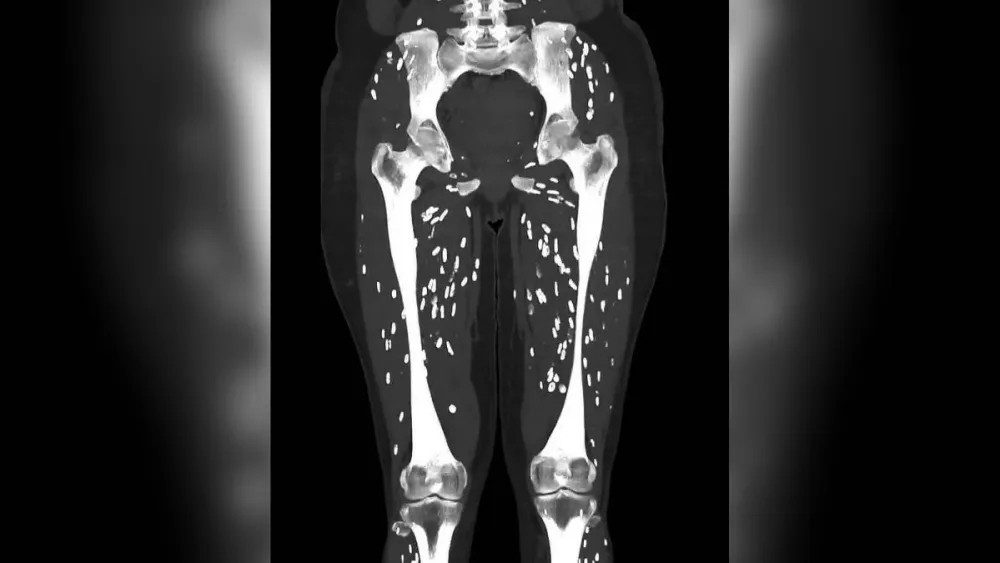

Um raio-x impressionante compartilhado por um médico no X, antigo Twitter, mostrou vários ovos de tênia (Taenia Solium) espalhados pelo corpo de um paciente.

O parasita forma um cisto duro e calcificado no músculo ou no cérebro, podendo parecer caroços na pele. Na tomografia, é possível ver várias manchas brancas.